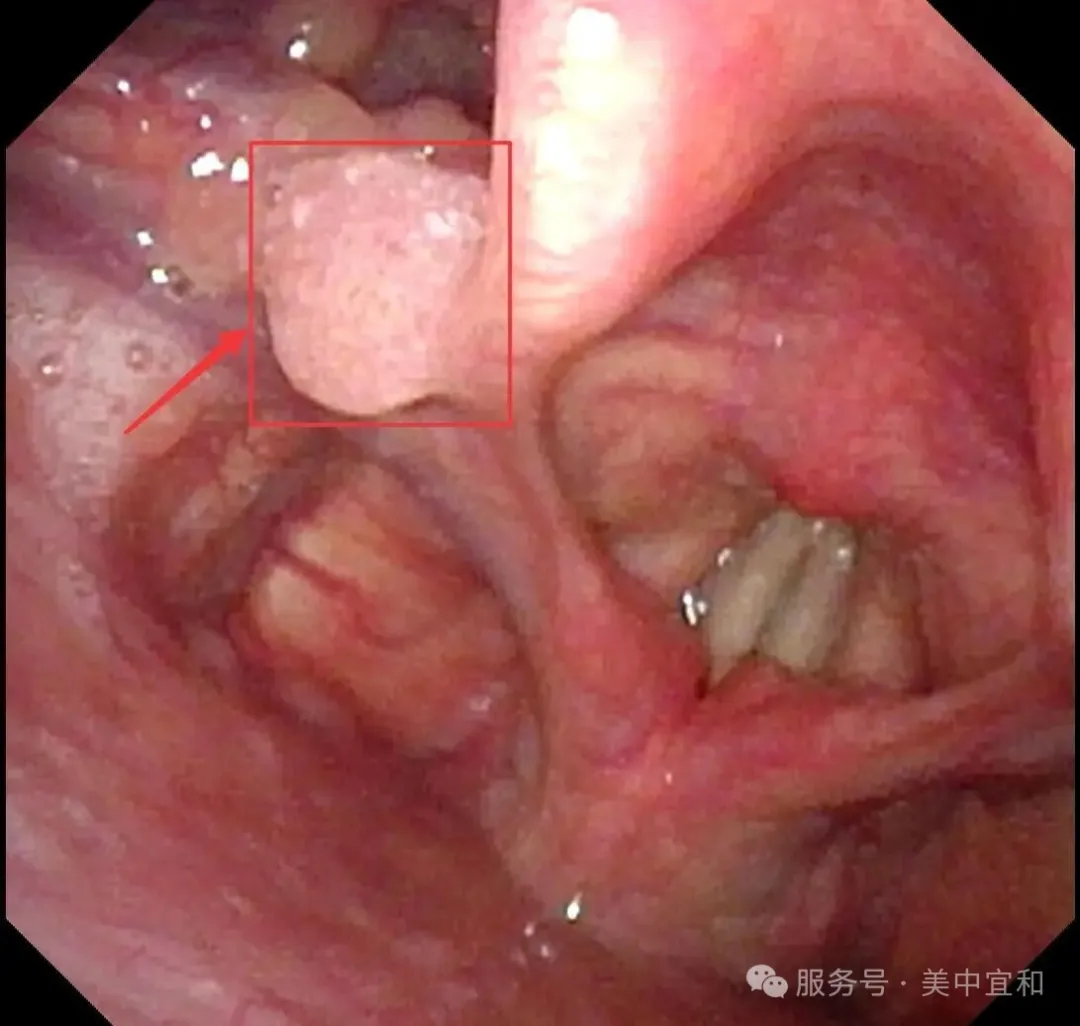

從(cong)消化內(nei)科(ke)無縫銜接到(dao)耳鼻喉科(ke),由于(yu)疑似腫物(wù)位于(yu)喉腔入口處的(de)會厭部(bu),王主(zhu)任馬上爲(wei)C先(xian)生(sheng)安(an)排(pai)了(le)更爲(wei)精(jīng)細的(de)電(dian)子(zi)鼻咽喉鏡檢(jian)查 ,确診爲(wei)會厭側乳頭狀瘤。

正常會厭部(bu)

會厭左側緣乳頭狀瘤

王主(zhu)任提到(dao),這種腫瘤絕大(da)多(duo)數(shu)爲(wei)良性病變,生(sheng)長(zhang)速(su)度相對緩慢,惡變的(de)風險較低,但存在(zai)播散到(dao)其他(tā)黏膜的(de)可(kě)能(néng)。若不及(ji)時治療,腫瘤可(kě)能(néng)累及(ji)并擴散至聲帶等(deng)部(bu)位,可(kě)能(néng)出現(xian)咽喉異物(wù)感,吞咽不适、聲音嘶啞,嚴重(zhong)時腫瘤會阻塞喉腔入口,還可(kě)能(néng)引起呼吸(xi)困難,增加(jia)了(le)治療難度,甚至需要做氣(qi)筦(guan)切開。所幸髮(fa)現(xian)及(ji)時,C先(xian)生(sheng)腫瘤病變還未波(bo)及(ji)到(dao)聲們(men)以(yi)下,王主(zhu)任建(jian)議手術(shù)治療,采用(yong)支撐喉鏡下微創手術(shù),通(tong)過(guo)喉鏡暴露腫瘤後(hou),使用(yong)低溫等(deng)離子(zi)将腫瘤完整切除,這種術(shù)式(shi)創傷小(xiǎo),可(kě)以(yi)最大(da)限(xian)度地保留會厭部(bu)的(de)正常功能(néng),并且有(yǒu)助于(yu)恢複。最終手術(shù)順利完成(cheng),用(yong)時20分(fēn),出血量僅1ml。